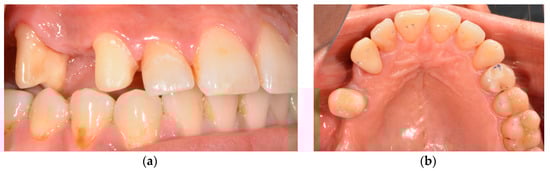

| Gender | female |

| Age | 32 |

| Implant position | Tooth 14 (upper left first premolar) |

| Diagnostic | Intraoral scans |

| Restorative | Intraoral scans with a scanbody |

| Chairside, computer-aided design and milling of the provisionalization | |

| Placement of the chairside LTT |